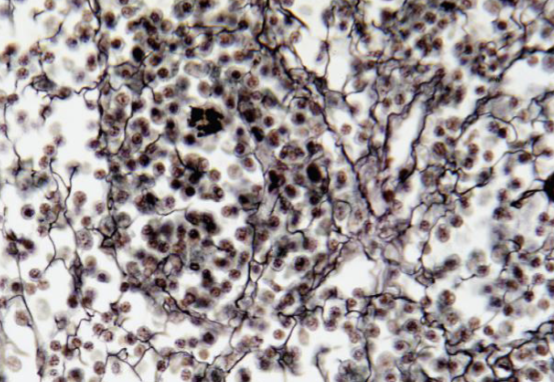

Identifique tipo de tejido conectivo

reticular

Indique sitio anatómico dónde se encuentra

higado